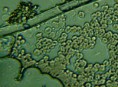

Mnohé štúdie dokazujú pozitívny efekt Bioquantu - jeho laserového žiarenia na postupnú elimináciu baktérií, vírusov či lariev parazitov migrujúcich v krvnom riečišti. Ide najmä o normalizáciu imunity, špecifickej i nešpecifickej. Navyše termodynamický efekt laseru pri ožarovaní krvi, ktorý síce náš organizmus nevníma a ľudské bunky neohrozuje, spôsobuje zvyšovanie termodynamickej teploty najmenších štruktúr - teda mikroorganizmov. Tieto následne ničí aktivovaná imunita a zvýšená baktericídna aktivita krvného séra. Sú zaznamenané pozitívne efekty pri vírusoch HIV/AIDS, vírusoch encefalitídy, pri borelióze, pri prevencii chrípky. O účinkoch na baktérie svedčí aj vysoká účinnosť pri výskytu akné baktérií. Prostredníctvom aktivácie porfírinov sa uvoľňujú voľné radikály a tým zabíjajú baktérie zvnútra..

Laserové ožarovanie krvi navodzuje i úpravu pomerov populácie T helperov a T supresorov smerom k normalizácii a úprave celkového počtu T lymfocytov a vyvoláva zmenu aktivity enzýmov imunokompetentných buniek. To je dôležité pre celom rade ďalších ochorení.